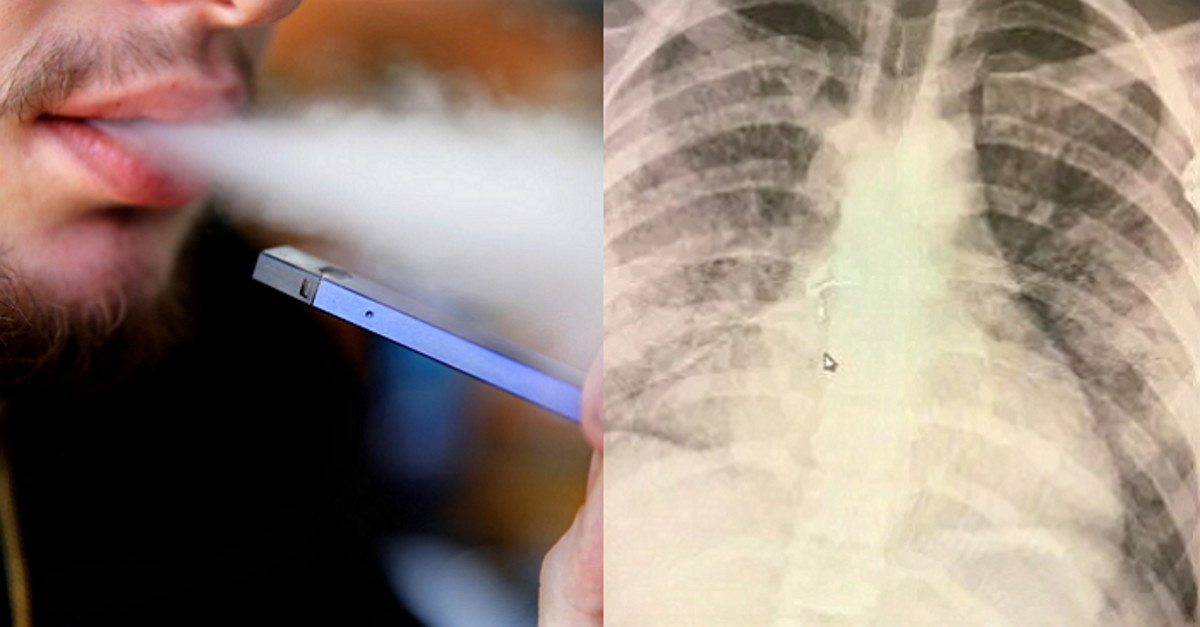

미국 일리노이주 출신의 18세 남성 아담 헤르겐리더(Adam Hergenreder)는 약 1년 전부터 USB 모양의 '쥴(JULL)' 전자담배를 피워왔다.

그런데 하루에 한 포드(액상 카트리지) 정도를 피운 아담은 최근 메스꺼움과 호흡 곤란 증세를 보여 병원으로 실려 왔다.

아담을 검진한 의료진은 "아담의 폐가 현재 70세의 폐와 비슷하다"는 충격적인 진단을 내렸다.

기사 이해를 돕기 위한 자료 사진 / vaporvanity